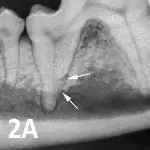

Type 1: There is alveolar bone loss adjacent to well-defined areas of tooth resorption. The lesion appears radiographically discrete and unaffected areas of the root appear normal. Normal periodontal ligament space is maintained at other areas of the tooth (See Figure 2A). If the lesion extends into the oral cavity, the tooth should be extracted.

Featured Image

Figure 2A

Type 1 resorption. Arrows point to distal root resorption lacuna with discernible periodontal ligament space.